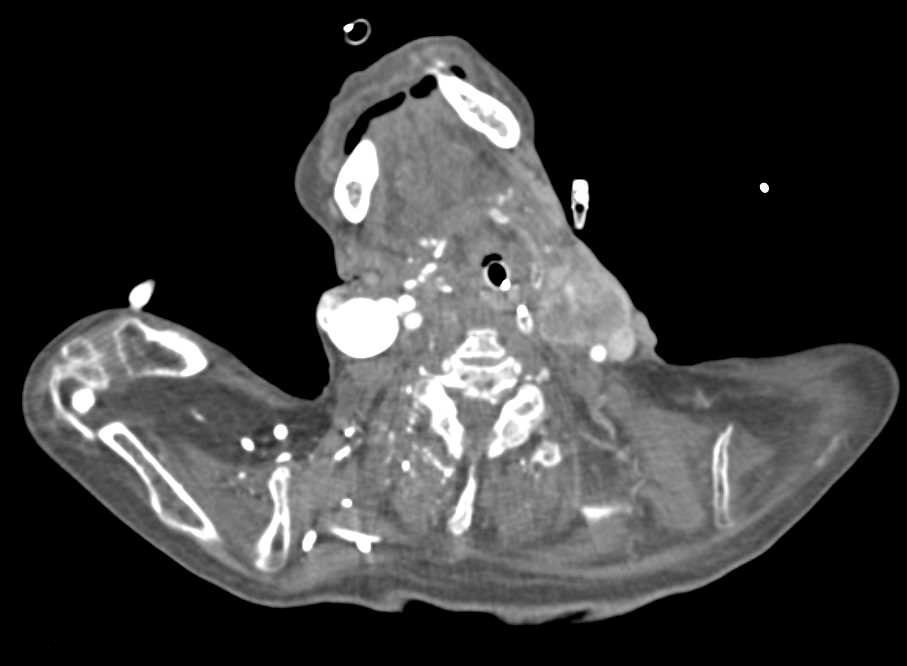

Orbital Fracture Post Repair